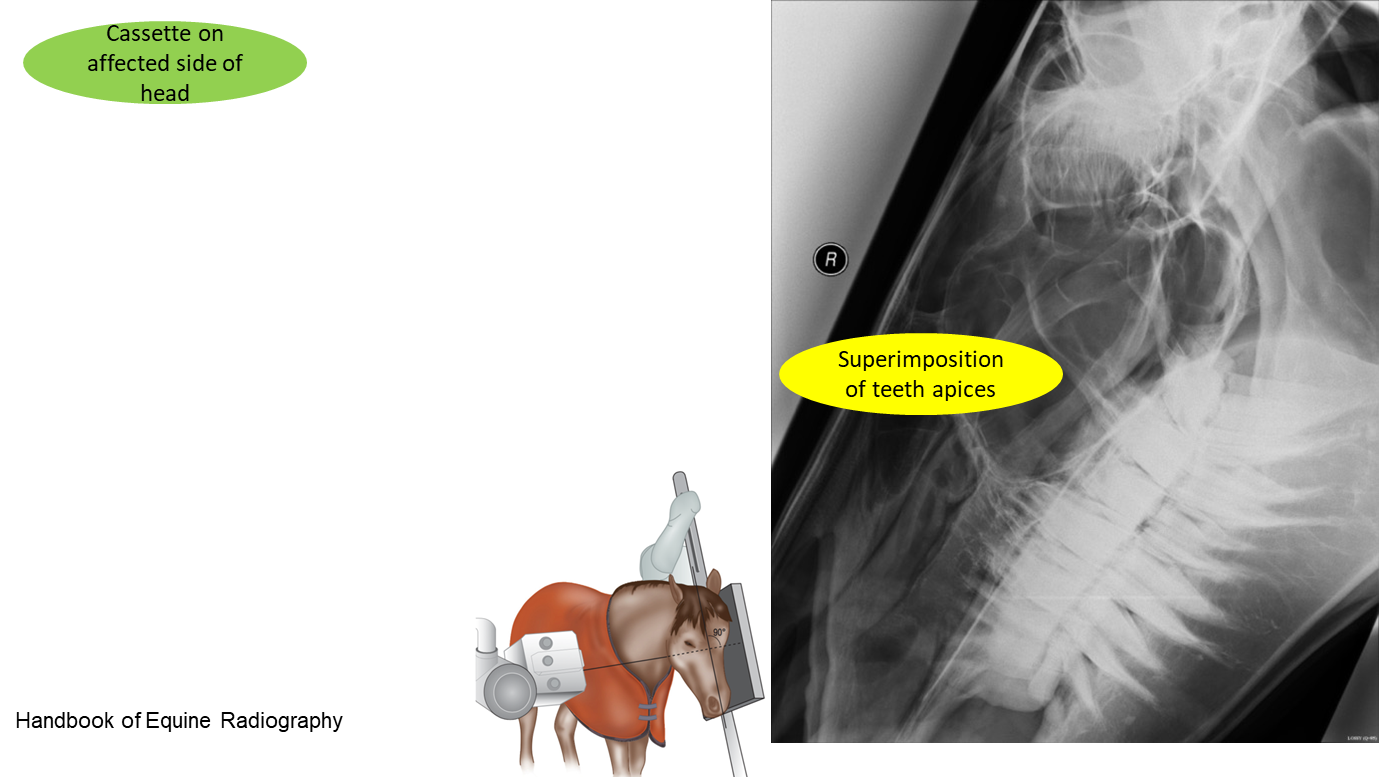

What is lateral oblique view used for? How is it taken?

Assess the periapical regions of the cheek teeth for evidence of infection

30° angulation maxillary arcades

45° angulation for mandibular arcades

No superimposition of teeth apices (cf. to latero lateral)

Normal anatomy in lateral oblique

Maxillar

Mandibular